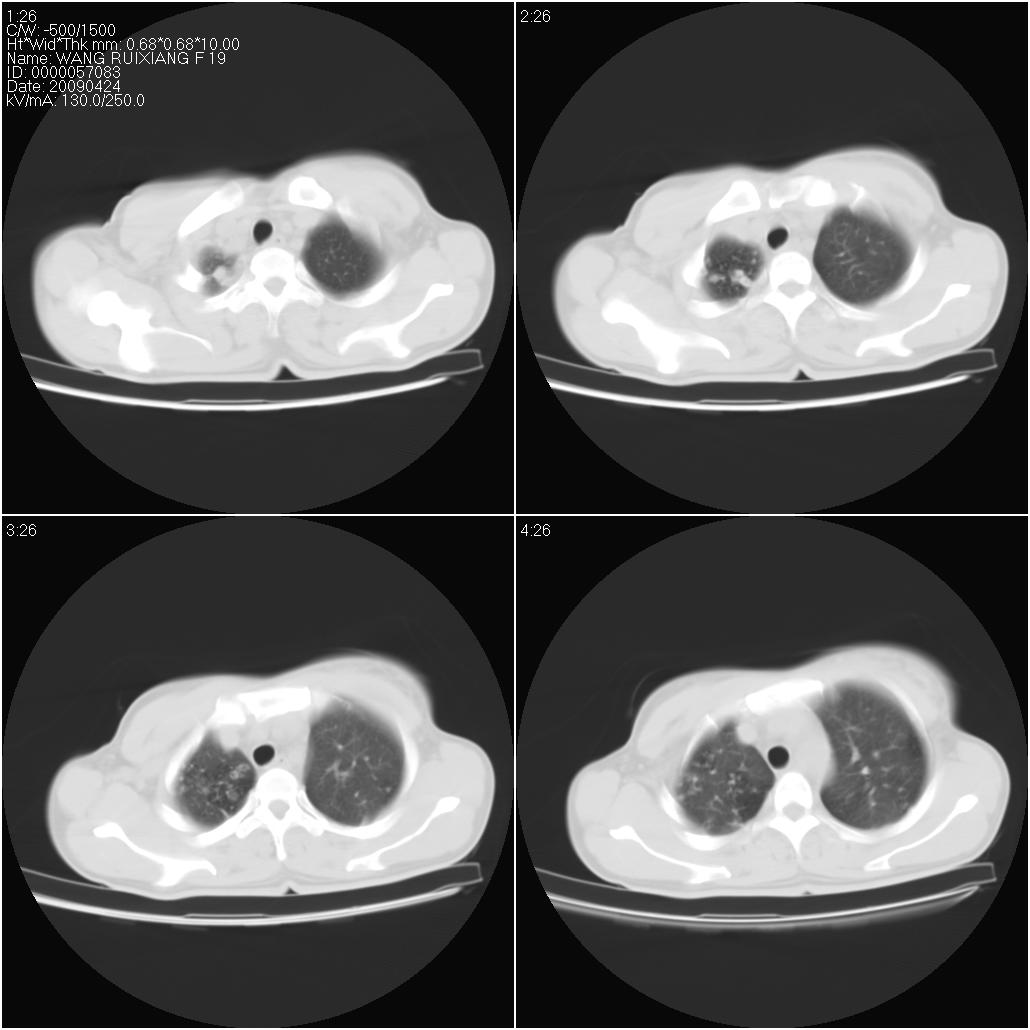

标题: CT19588:女性,39岁。患者胸闷不适,上楼时气喘。 [打印本页]

标题: CT19588:女性,39岁。患者胸闷不适,上楼时气喘。

片子上的年龄为19岁,是操作错误。该患者于去年5月份曾做平片和ct扫描,和这一次的ct检查没有明显变化。当时诊断为肺结核,进行抗痨治疗至今,但没有改善。呼吸功能试验为混合型呼吸困难。除此之外,该患者没有其他方面没有的临床症状和体征

两肺见斑点片状阴影,部分病灶密度较高,右下肺见小囊状及柱状蜂窝状阴形,考虑为两肺结核以阵旧性为主,右下肺支扩。